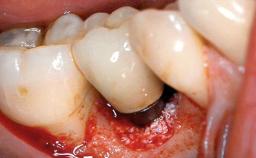

A 35-year old female patient was referred to the Department of Oral Surgery and Stomatology at the University of Bern, Switzerland, for examination of an implant site that had exhibited clinical signs of slightly delayed wound healing. In addition, the referring clinician found no evidence for a facial bone wall when she raised a flap to gain access to the implant for abutment connection. Four months earlier, she had inserted a bone-level implant in a single-tooth gap, where the lateral incisor had been extracted due to a chronic periapical lesion on the mesial aspect of the root. Implant placement was combined with simultaneous bone augmentation using deproteinized bovine bone mineral (DBBM, Bio-Oss®; Geistlich, Wolhusen, Switzerland) and a collagen membrane (Bio- Gide®; Geistlich), followed by primary wound closure. The patient also provided the postsurgical radiograph that displayed the implant with a 3.5-mm healing cap.